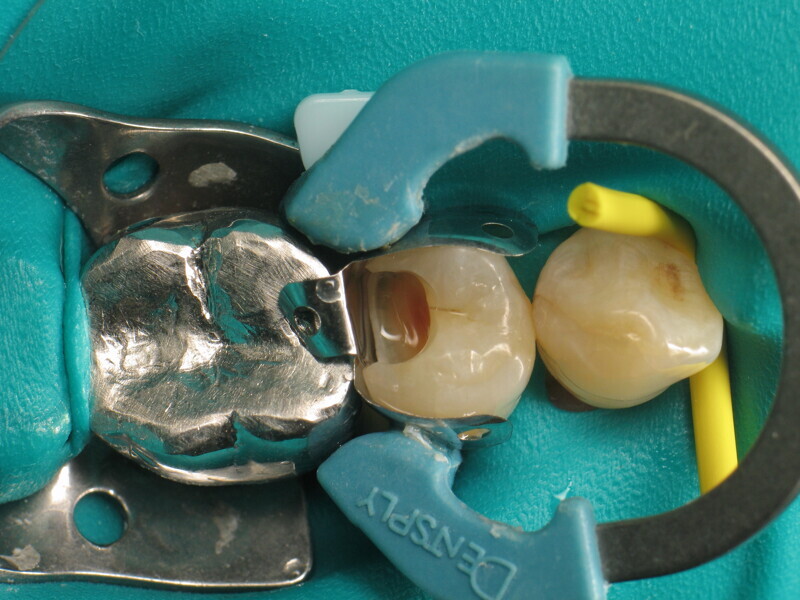

Le cas clinique décrit dans cet article porte sur une cavité de classe II sur une prémolaire (45) qui sera restaurée à l’aide d’un composite thermovisqueux (Fig. 1). La dent est isolée avec une digue en latex (Fig. 2). La cavité de classe II est ensuite nettoyée (Fig. 3). Afin d’obtenir une paroi distale anatomiquement correcte, une matrice, un coin et un anneau sont placés (Fig. 4). L’émail dentaire est ensuite mordancé pendant 30 secondes et la dentine pendant 15 secondes (Conditioner 36, Dentsply Sirona ; Fig. 5) puis rincé abondamment (Fig. 6). En raison de la faible épaisseur de dentine restante, une protection pulpaire (Telio Desensitizer, Ivoclar) est également appliquée (Fig. 7). L’adhésif (Futurabond DC, VOCO) est déposé dans la cavité pendant 20 secondes puis séché 5 secondes sous un jet d’air non gras et enfin, photopolymérisé pendant 10 secondes (Figs. 8 et 9). Pour un mouillage optimal, le fond de la cavité est recouvert d’un composite fluide extrêmement fin (GrandioSO Light Flow, A3.5, VOCO) et durci en 20 secondes (Figs. 10 et 11).